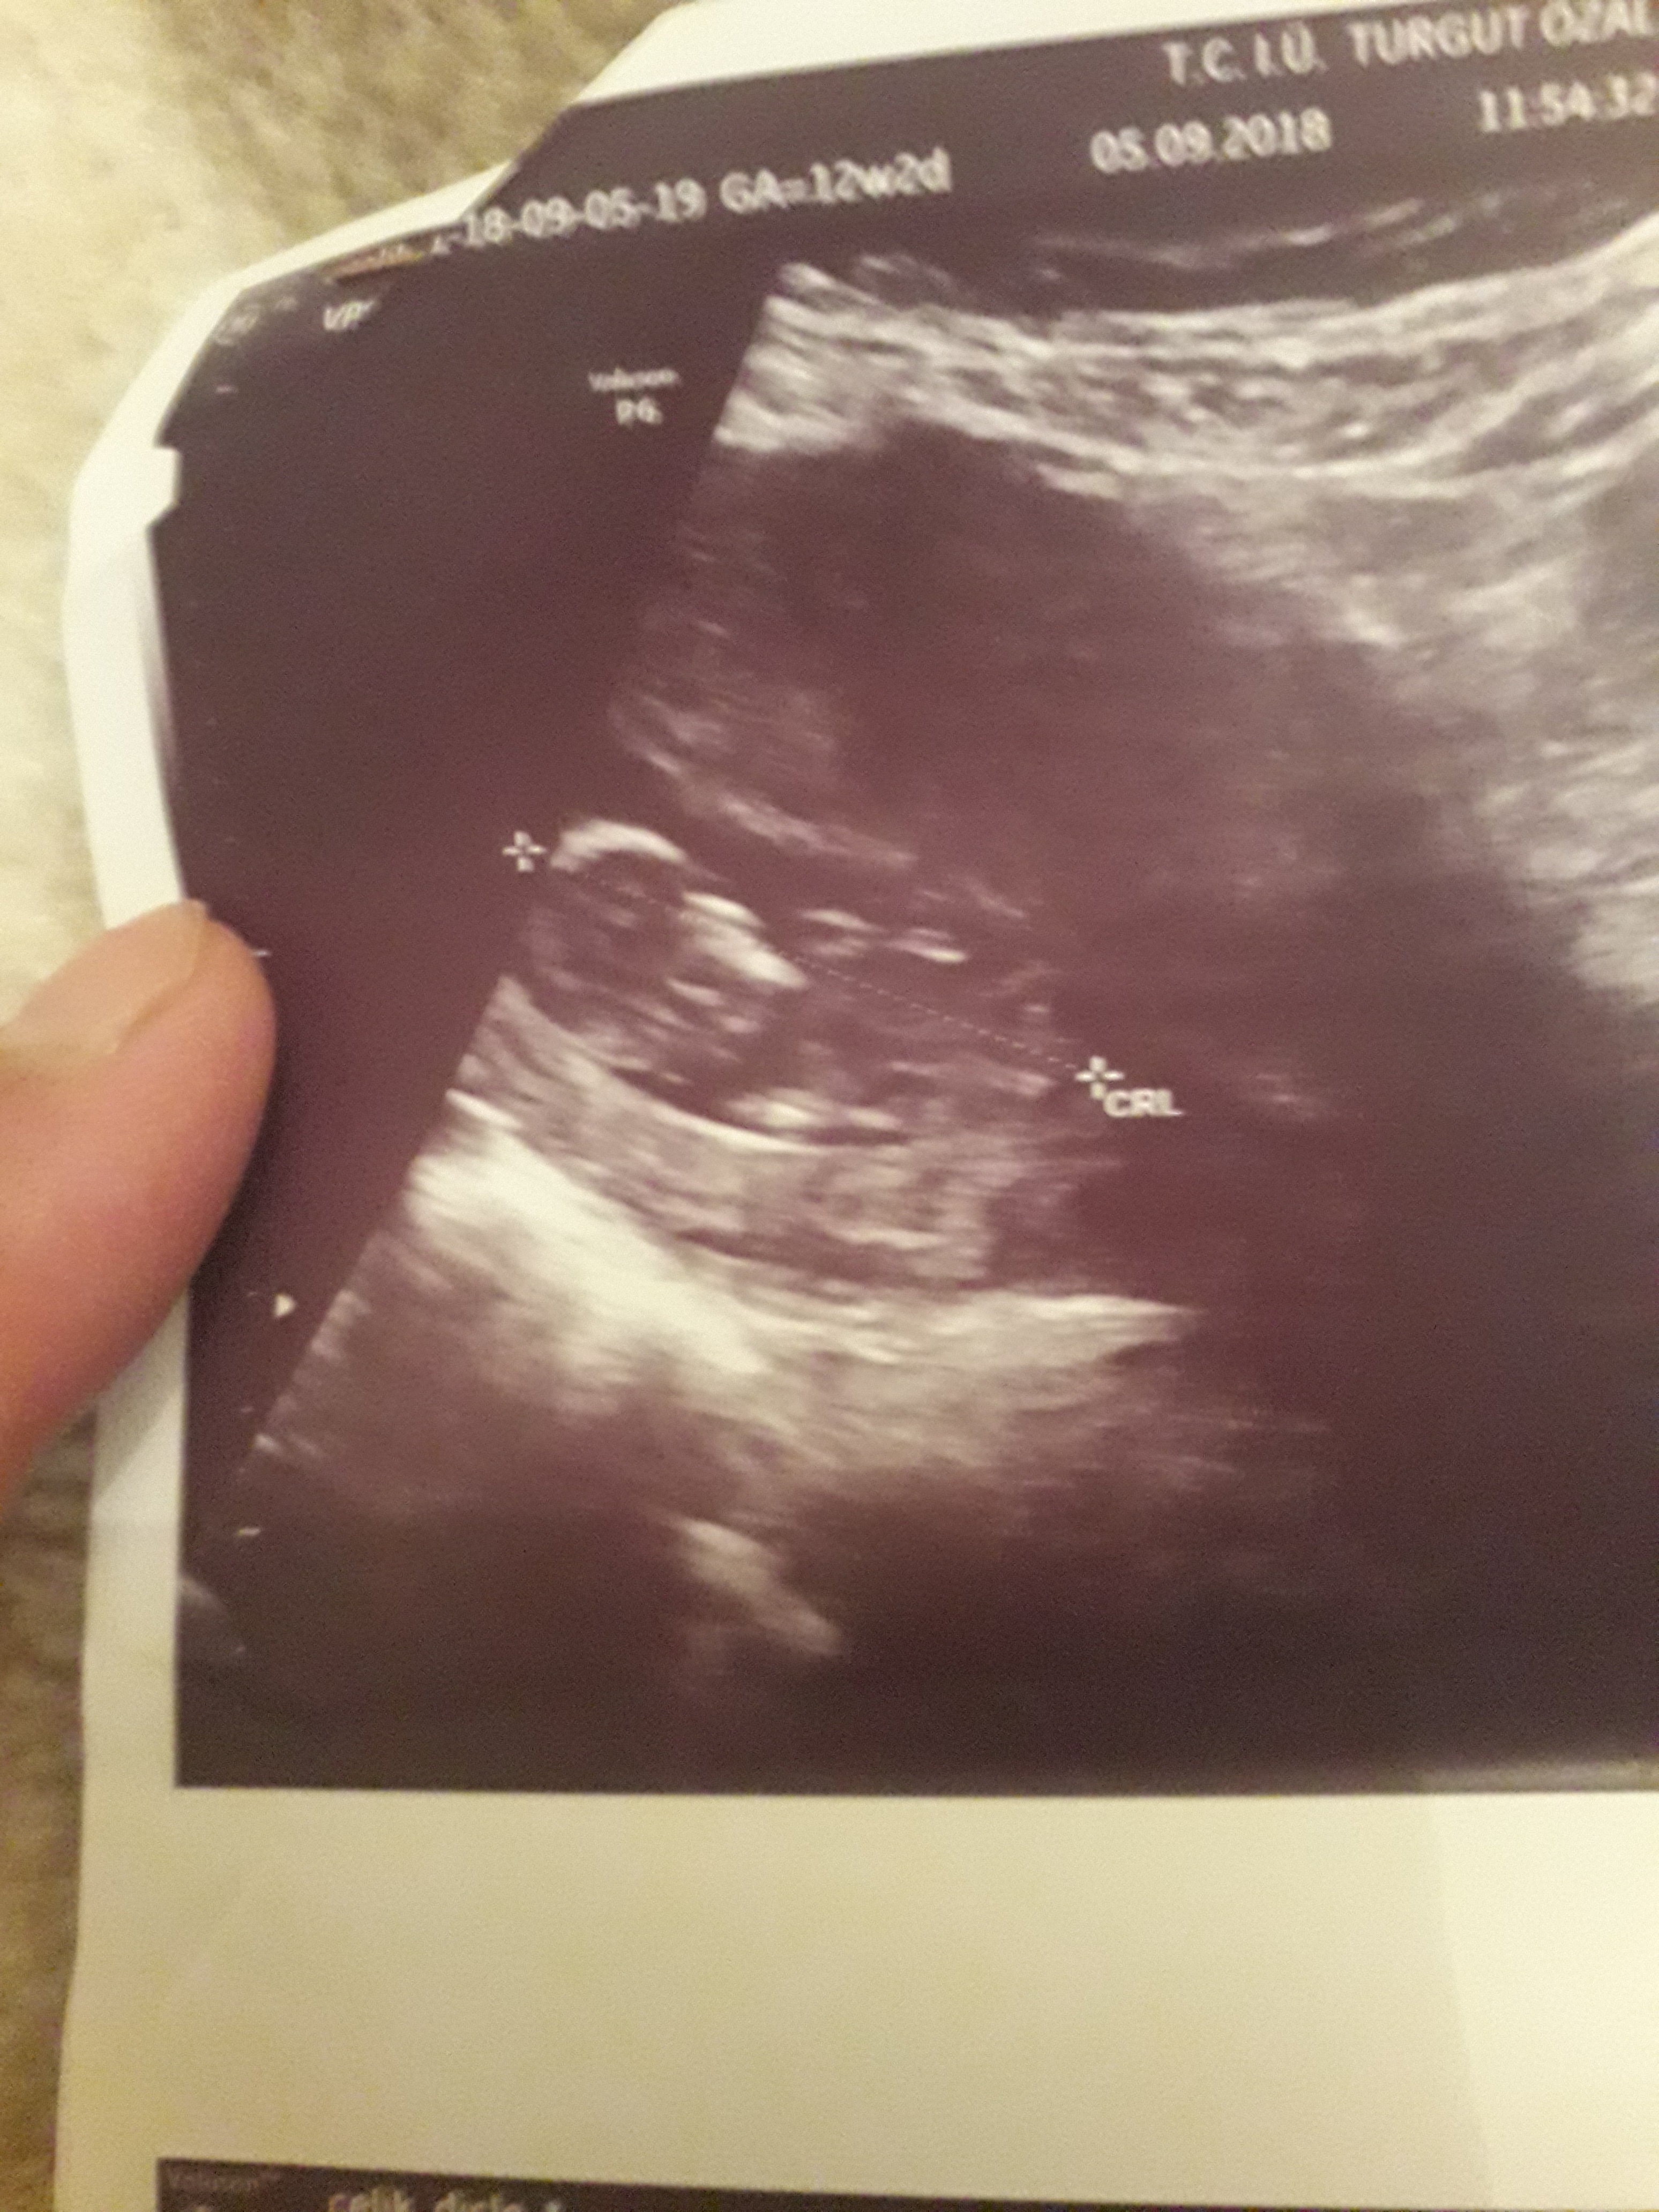

Dun malatyada verildi 12 +4 gunluk lutfen yorumlayin

Dun verildi 12 haftalik lutfen yorumlayin

Görsellerde nub çıkıntısı belli değil . Ultrasonu yapan doktor cinsiyeti hakkında bilgi vermiştir mutlaka ama şunu belirtmeden geçmeyeyim. Bu haftalarda cinsiyet tahmininde yanılma payı çok yüksek 17-19 ve 20 ci haftalarda bebeğin cinsiyetini net olarak öğrenebilirsiniz.